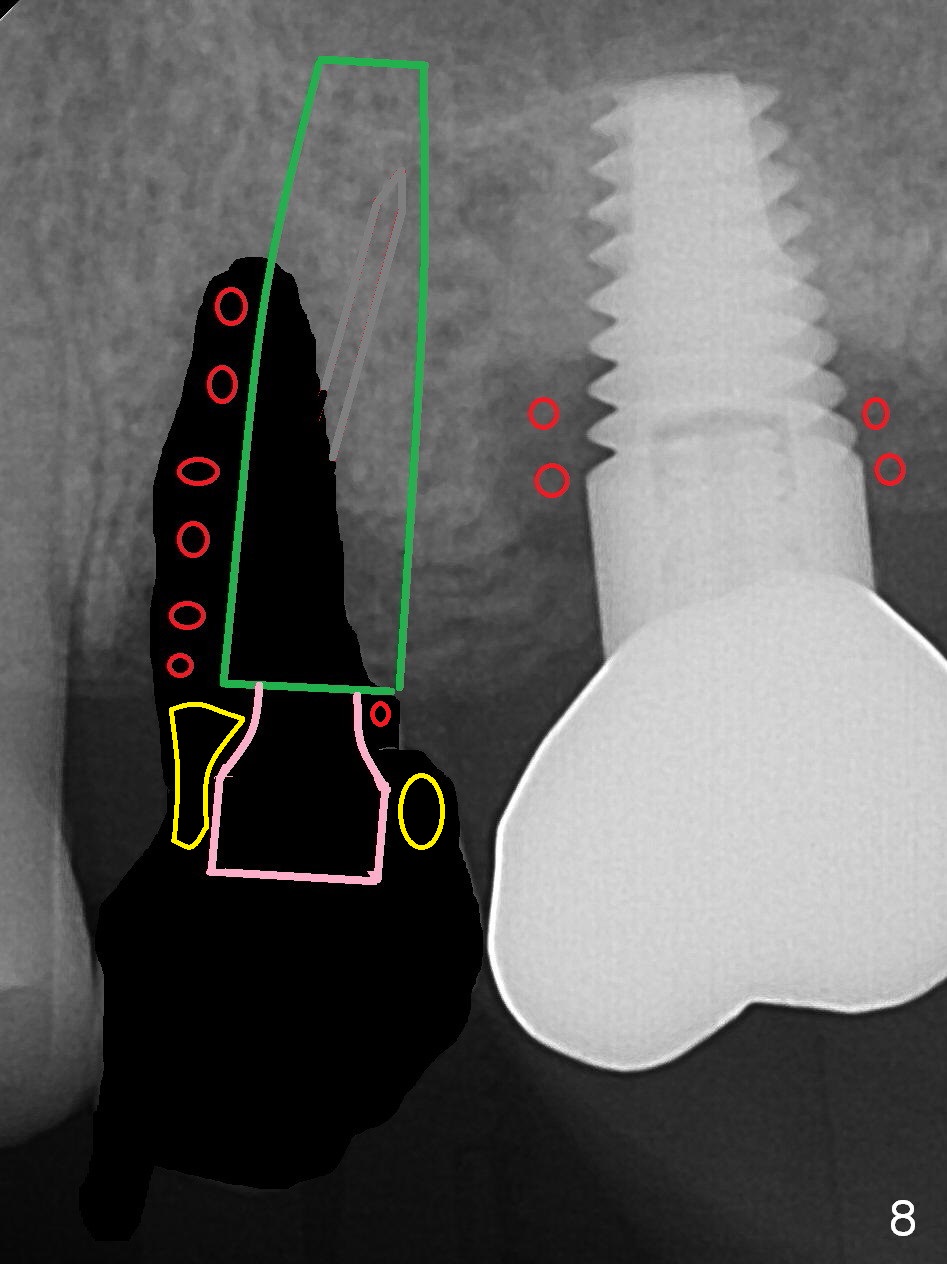

To compensate for bruxism, the implant at #13 should be as large and long as possible. After extraction (Metronidazole), take PVS impression of the socket. Start osteotomy in the distal wall of the socket (Fig.7 red). The initial depth is 11 mm (gingival level). Increase the depth once the trajectory is confirmed (Fig.9). After implant placement (Fig.8 green), place bone graft (red circles) in the mesial portion of the socket as well as in the coronal portion of the implant at #14 (incision). Use a healing abutment (pink), collagen plug (yellow) and suture to close the socket opening.